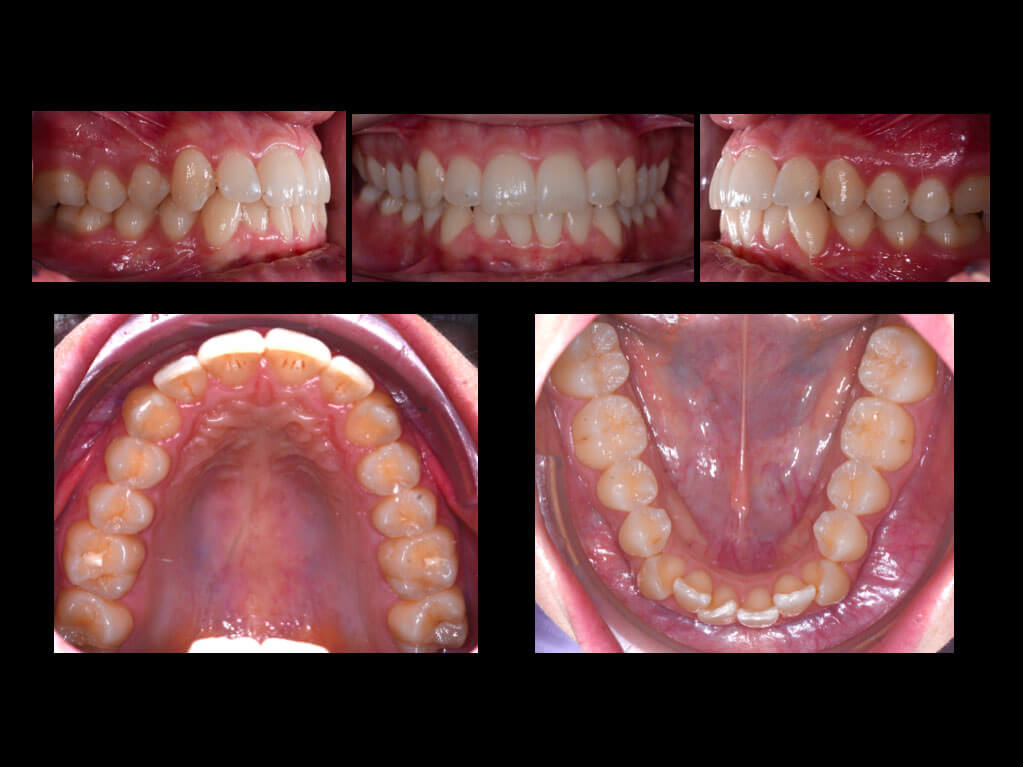

Case of lower crowding

The female patient came to our attention for the resolution of crowding in the lower arch. She requested treatment with an “aesthetic and comfortable” appliance. Intraoral analysis showed a Class I molar and canine relationship on the right and a mild Class III molar and canine relationship on the left. The dental midlines did not coincide, with the upper midline deviated towards the left side of the patient in relation to the facial midline. Overjet and overbite were within normal limits. At the level of the lower arch there was a medium amount of crowding concentrated mainly at the level of the anterior sextant (1).

The radiographic analysis showed the presence of all the dental elements, with a good state of dental health (2). The proposed orthodontic treatment was to use the F22® aligner system with a series of 10 upper and 16 lower steps, particularly suitable in skeletal Class III cases with a hyperdivergent facial pattern, to avoid loss of anterior anchorage.

The treatment plan involved the use of only two grip points at the level of elements 3.3 (vestibular) and 4.3 (lingual) and the execution of stripping of 0.2 mm from distal 3.4 to distal 4.4 to achieve resolution of crowding without excessive proclination of the mandibular anterior elements.